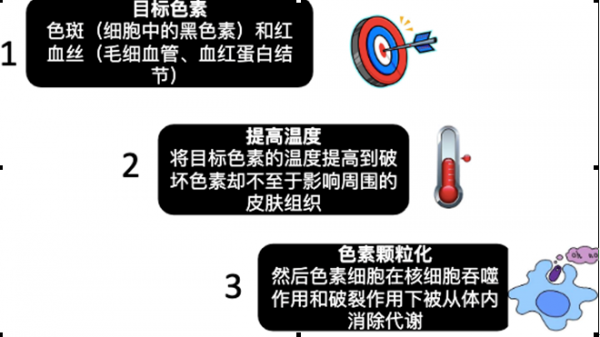

毕业之后自己工作了来到纽约,有更多的渠道去了解不同的讯息了。虽然我还是没有勇气去在脸上动真刀,但是我迈出了医美的第一步:激光和光子嫩肤。我去咨询了专业的医美医生,确认了我脸上沉积的色素是可以通过激光和强脉冲光消除的,于是二话不说的开始了我的疗程。当时住在新泽西找了一个在fort Lee的韩国医生,价格说实话也不便宜,让我一次交了5次的费用,一共是2500,也就是500一次。但是我后来转念一想,如果能快速有效的解决我的色斑问题,那这点钱花的也完全值啊。我买了那么多美白精华护肤品化妆品,加起来早就超过我现在做医美花的钱了。

毕业之后自己工作了来到纽约,有更多的渠道去了解不同的讯息了。虽然我还是没有勇气去在脸上动真刀,但是我迈出了医美的第一步:激光和光子嫩肤。我去咨询了专业的医美医生,确认了我脸上沉积的色素是可以通过激光和强脉冲光消除的,于是二话不说的开始了我的疗程。当时住在新泽西找了一个在fort Lee的韩国医生,价格说实话也不便宜,让我一次交了5次的费用,一共是2500,也就是500一次。但是我后来转念一想,如果能快速有效的解决我的色斑问题,那这点钱花的也完全值啊。我买了那么多美白精华护肤品化妆品,加起来早就超过我现在做医美花的钱了。 做完是不是超级光滑?虽然我不敢说无暇,但是我现在就完全从美妆爱好者变身素颜控!以前九点上课宁愿早上6点半7点起床,底妆修容高光眼影腮红眼线睫毛口红一个都不能落下,妆必须得完完整整了才出门。

美容医师建议,做完第一个疗程的治疗后(期间间隔一个月一次),建议半年至一年再做单独的一次巩固和消除一些因为日晒和辐射产生的一些新的色斑。

美容医师建议,做完第一个疗程的治疗后(期间间隔一个月一次),建议半年至一年再做单独的一次巩固和消除一些因为日晒和辐射产生的一些新的色斑。 因为IPL强脉冲光是无创的,感觉比之前做激光还要更舒服一些,对于我这种曾经做过激光的人来说,连麻药都不用敷。基本流程都和激光一模一样,只是IPL非常考验机器的设置和参数的调整。这家位于曼哈顿中城的Medical Spa使用的Viora是市面上最贵最先进有效的机器,比之前我随便找的Spa的国产IPL机器效果强100倍不说,也比我之前用的激光刺激小。其实除了纹身这样的色素沉积,好的机器的IPL都可以实现。

因为IPL强脉冲光是无创的,感觉比之前做激光还要更舒服一些,对于我这种曾经做过激光的人来说,连麻药都不用敷。基本流程都和激光一模一样,只是IPL非常考验机器的设置和参数的调整。这家位于曼哈顿中城的Medical Spa使用的Viora是市面上最贵最先进有效的机器,比之前我随便找的Spa的国产IPL机器效果强100倍不说,也比我之前用的激光刺激小。其实除了纹身这样的色素沉积,好的机器的IPL都可以实现。